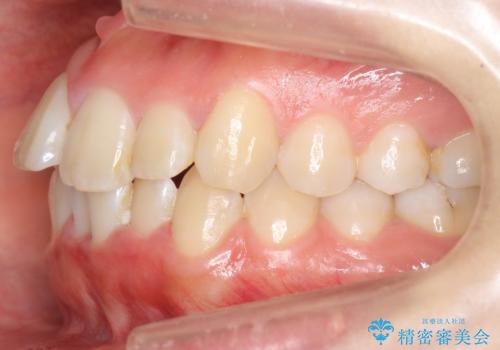

上下の前歯のがたつき 歯を抜かずに矯正

- 上下の前歯のがたつきを主訴に来院。

歯を抜かずに前歯を揃えています。

奥歯を後ろに下げたりなどはしていません。

奥歯を外に広げ、前歯中心に歯を少し削っていますが、健康には問題ない範囲で行なっています。